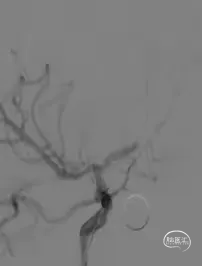

DSA提示右侧MCA、ACA重度狭窄。

全麻下行右侧ACA、MCA球囊扩张支架植入术。

球囊扩张后管腔较前明显好转。

造影见支架贴壁良好,血流通畅。